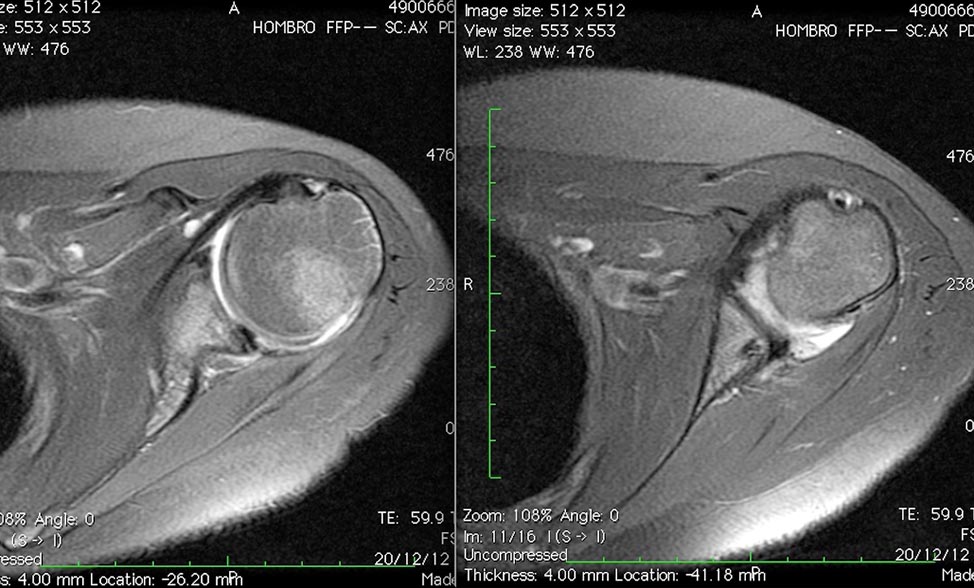

Contamos con RNM postoperatoria a los 6 meses, que muestra las anclas en correcta ubicación y la cabeza humeral centrada en la glena, con un labrum posterior restituido (fig. 4).